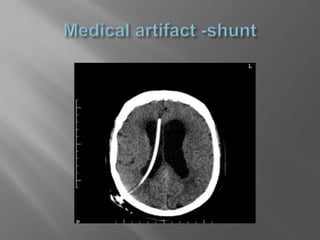

 Look atold images and reports  Check for movement artifacts and medical artifacts  Do not view only a single slice in isolation  If you suspect brain stem pathology ,consider MRI

 Check for movement artifacts and medical

artifacts